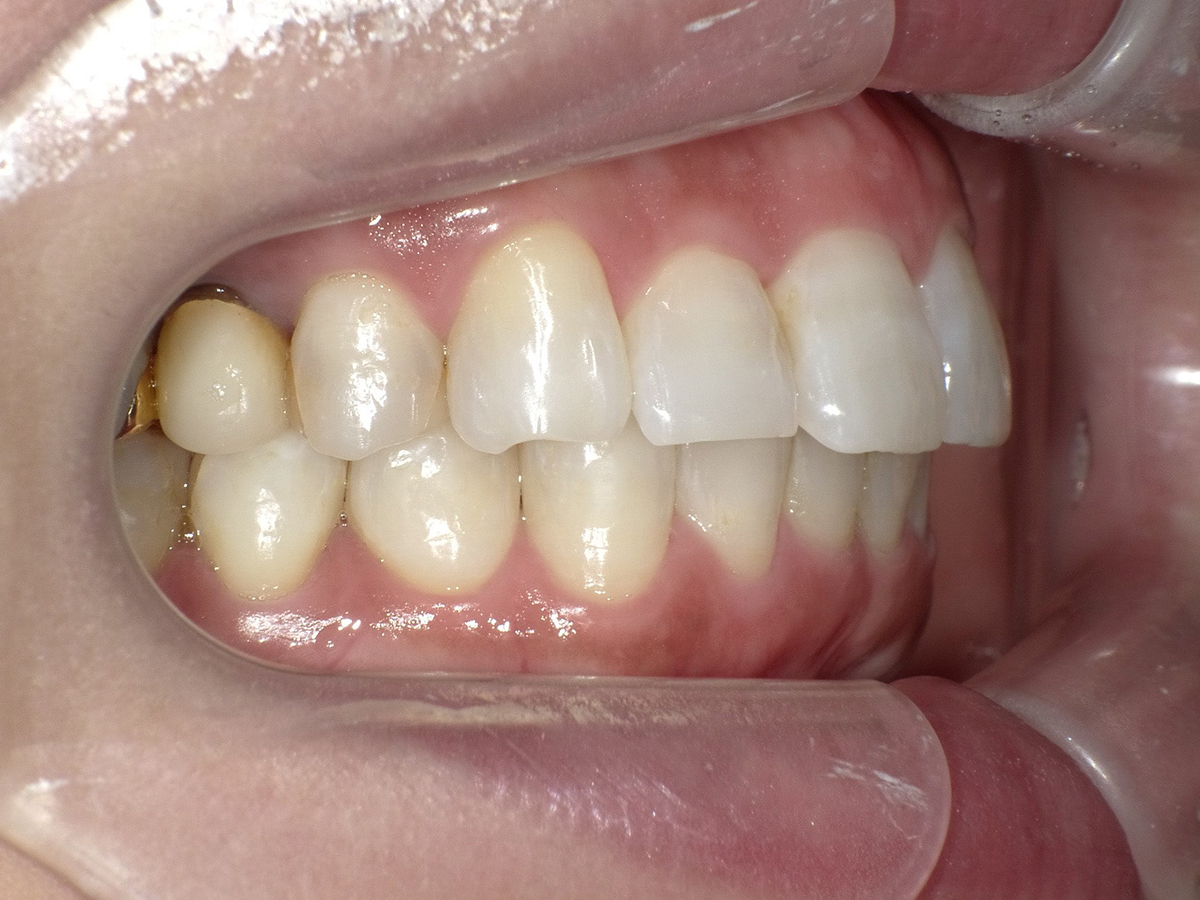

症例②

症例2_治療前 症例2_治療後

年齢・性別 31才・男性

治療方法 ブラケット矯正

治療期間 3年

治療総額 850,000円

特記事項 抜歯あり(4本抜歯)